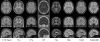

Multi-contrast PD126 and CTRL17 templates

Presenting PD126 and CTRL17: population-based multi-contrast templates for 126 Parkinson’s patients and 17 controls. These templates provide anatomical structural references for spatial normalization and structural segmentation of Parkinson's imaging data in the nine available contrasts: T1w (MPRAGE), T2*w, T1-T2* fusion, R2*, T2w, PDw, fluid-attenuated inversion recovery (FLAIR), neuromelanin-sensitive imaging, susceptibility-weighted imaging. The accompanying CTRL17 template facilitates group-wise analyses between Parkinson's and healthy controls. The templates are in stereotaxic space and are available in three different resolutions: 1×1×1 mm, 0.5×0.5×0.5 mm, and sectional 0.3×0.3×0.3 mm.